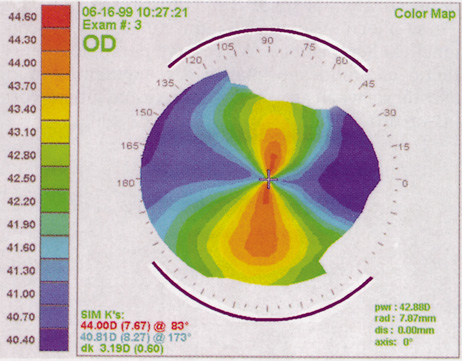

Computed corneal topography may be helpful from both a diagnostic perspective and as an aid to preoperative surgical planning. The diagnostic value of corneal topography is most obvious when keratoconus or irregular astigmatism is suspected. In cases with irregular astigmatism, superficial keratectomy or excimer phototherapeutic keratectomy may be indicated before cataract surgery, particularly when the relevant pathology precludes accurate keratometry.

In some cases, corneal topography is an invaluable aid in surgical planning as well. In patients with high astigmatism, the topography can indicate the best meridian for placement of limbal relaxing incisions (Fig. 5). The topography also may be used to confirm the keratometric measurements.